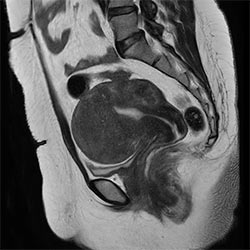

In a society where reimbursements are declining and chronic conditions lead to increased MR procedures and longer waiting times, there is ever increasing pressure on the radiology department. Today, further attempts to accelerate, compromise image quality or are limited to a narrow range of scans. Therefore, to meet the increased demand for productivity, a technology break-through in acceleration is still required. Leveraging our long standing leadership position in speed (i.e. SENSE), Philips brings compressed SENSE, a breakthrough in productivity.

Our goal is to reduce scan time, but we want the same image quality as before”

Sabine Sartoretti, MD, Head of Neuroradiology, Institute of Radiology and Nuclear Medicine, Kantonsspital Winterthur, Switzerland

Learn more about the main principles of Compressed SENSE and how it introduces a paradigm shift in productivity, how Compressed SENSE was designed around image quality, and how it advances productivity for clinical MR imaging.

Read about the experiences from Kantonsspital Winterthur (Switzerland) who experienced Compressed SENSE to be a simple yet powerful way to accelerate MRI scanning for different contrast types and sequences, in 2D as well as 3D.